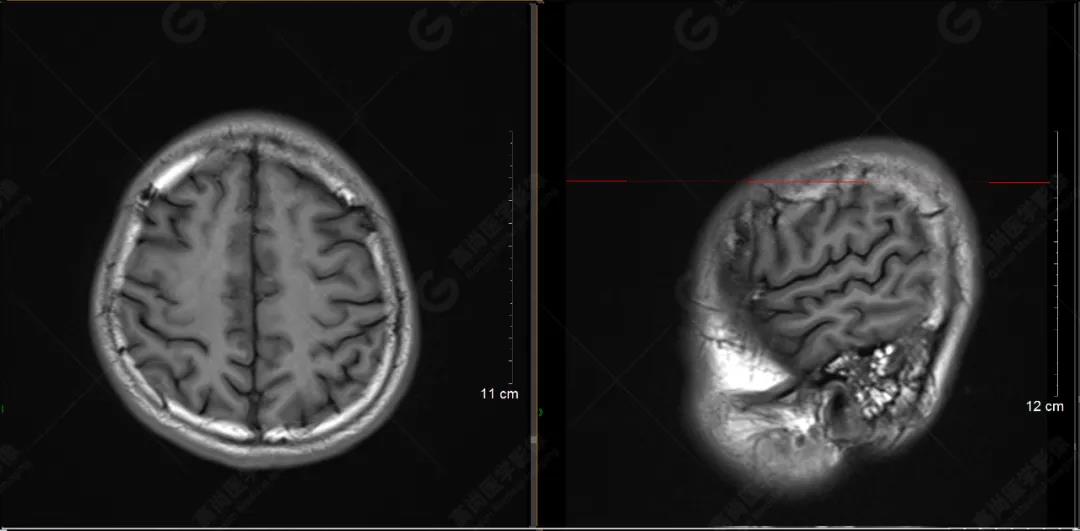

以下是T1WI軸位掃描及矢狀位掃描:

雙側(cè)大腦半球?qū)ΨQ,灰白質(zhì)對比正常,顱內(nèi)未見異常信號影。腦室系統(tǒng)未見擴(kuò)大,中線結(jié)構(gòu)居中。腦溝、裂未見增寬。幕下小腦、腦干未見異常。矢狀位示垂體形態(tài)、大小級信號未見異常。所示左側(cè)乳突內(nèi)見多發(fā)短T1長T2信號影。

顱腦MRI平掃未見明顯異常,左側(cè)乳突內(nèi)積血,建議補(bǔ)充SWI檢查。(左側(cè)為薄層原始圖像,右側(cè)為后處理5mm圖像)